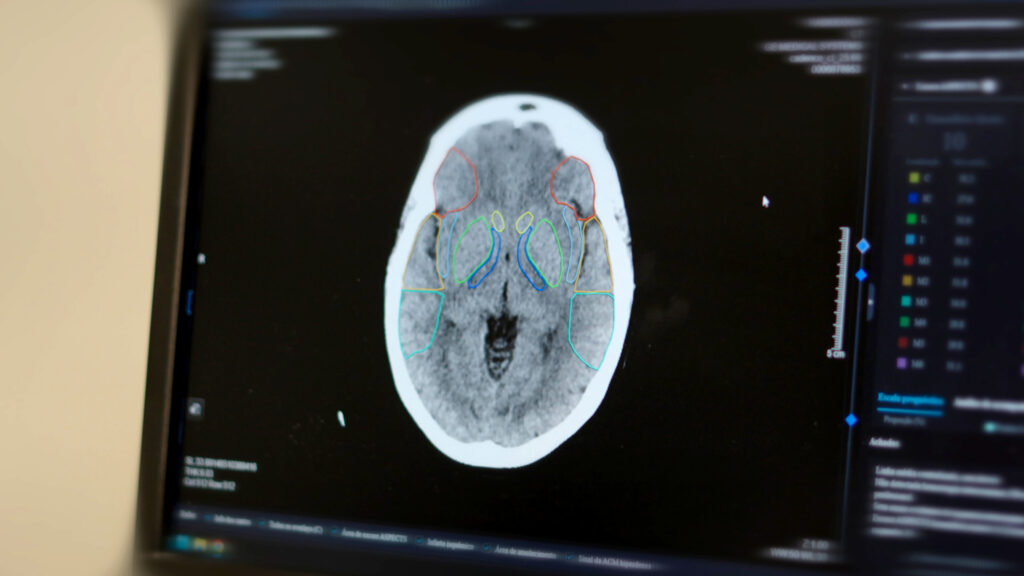

Nos laudos, a IA atua como um sistema avançado de reconhecimento de padrões. A partir da análise dos exames e do cruzamento com um banco de dados de grande escala, a tecnologia sugere possibilidades diagnósticas e destaca achados relevantes, auxiliando o médico radiologista na condução do laudo com mais segurança, consistência e padronização.

• A Inteligência Artificial utiliza algoritmos de Deep Learning (aprendizado profundo) para realizar uma leitura inicial das imagens em apenas cinco segundos.